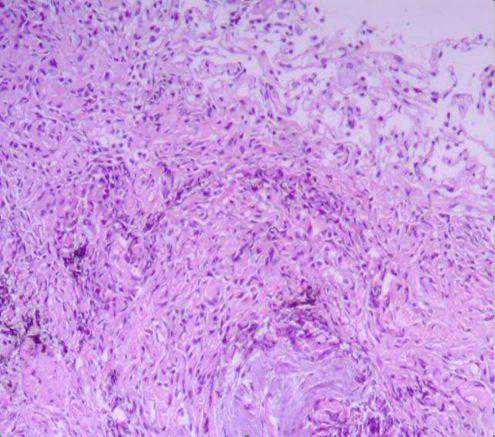

纤支镜检查镜下均以非特异性炎症改变为主(如图9-10),病理示淋巴细胞、中性粒细胞等炎性细胞侵润(图11)。对于肺隔离症的诊断或鉴别诊断所起作用较小。

图11肺泡间淋巴细胞及中性粒细胞侵润